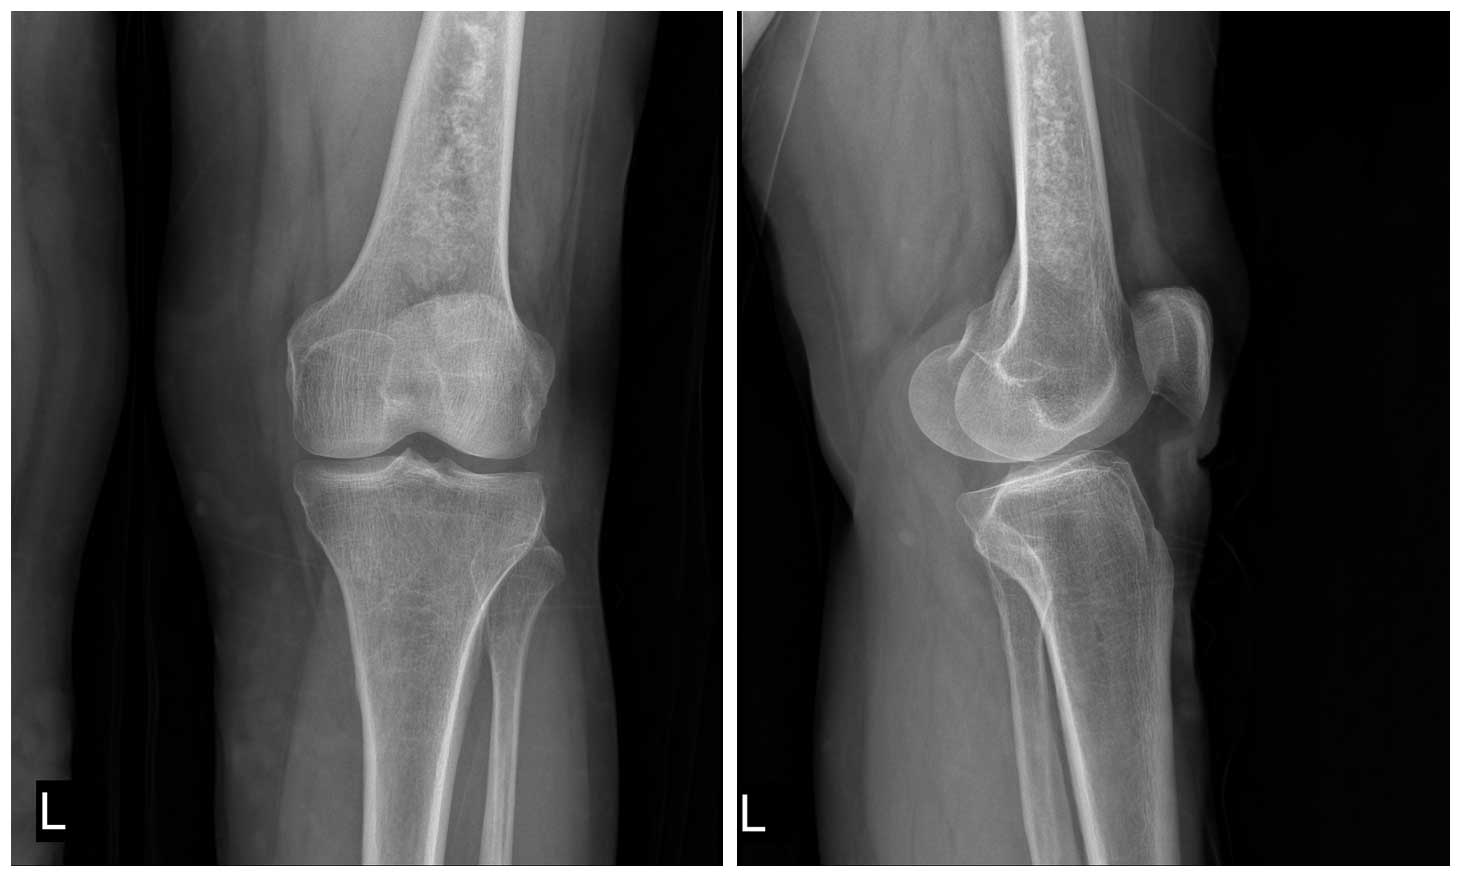

Ameliyat Öncesi: Röntgende distal femur yerleşimli düzensiz sınırlı kıkırdak doku tümörü görülmekte.